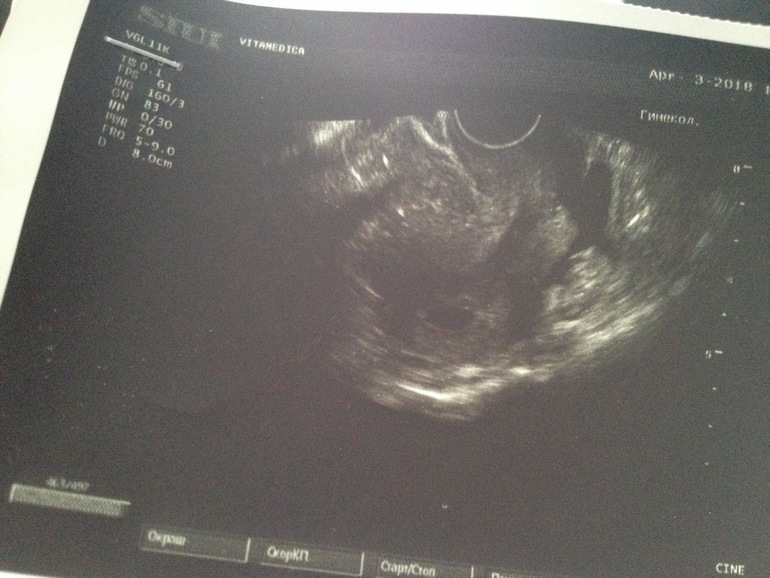

Подскажите все от хорошо с УЗИ.

Поставили срок 5 недель.

У многих на фотографиях УЗИ уже что-то заметно,а я почему-то по-моему просто вижу пустое яйцо

Первое УЗИ 5+3 пя 0.9 см и все! Не переживайте, через недельку уде ктр 0.4 и сердечко))) просто рано еще